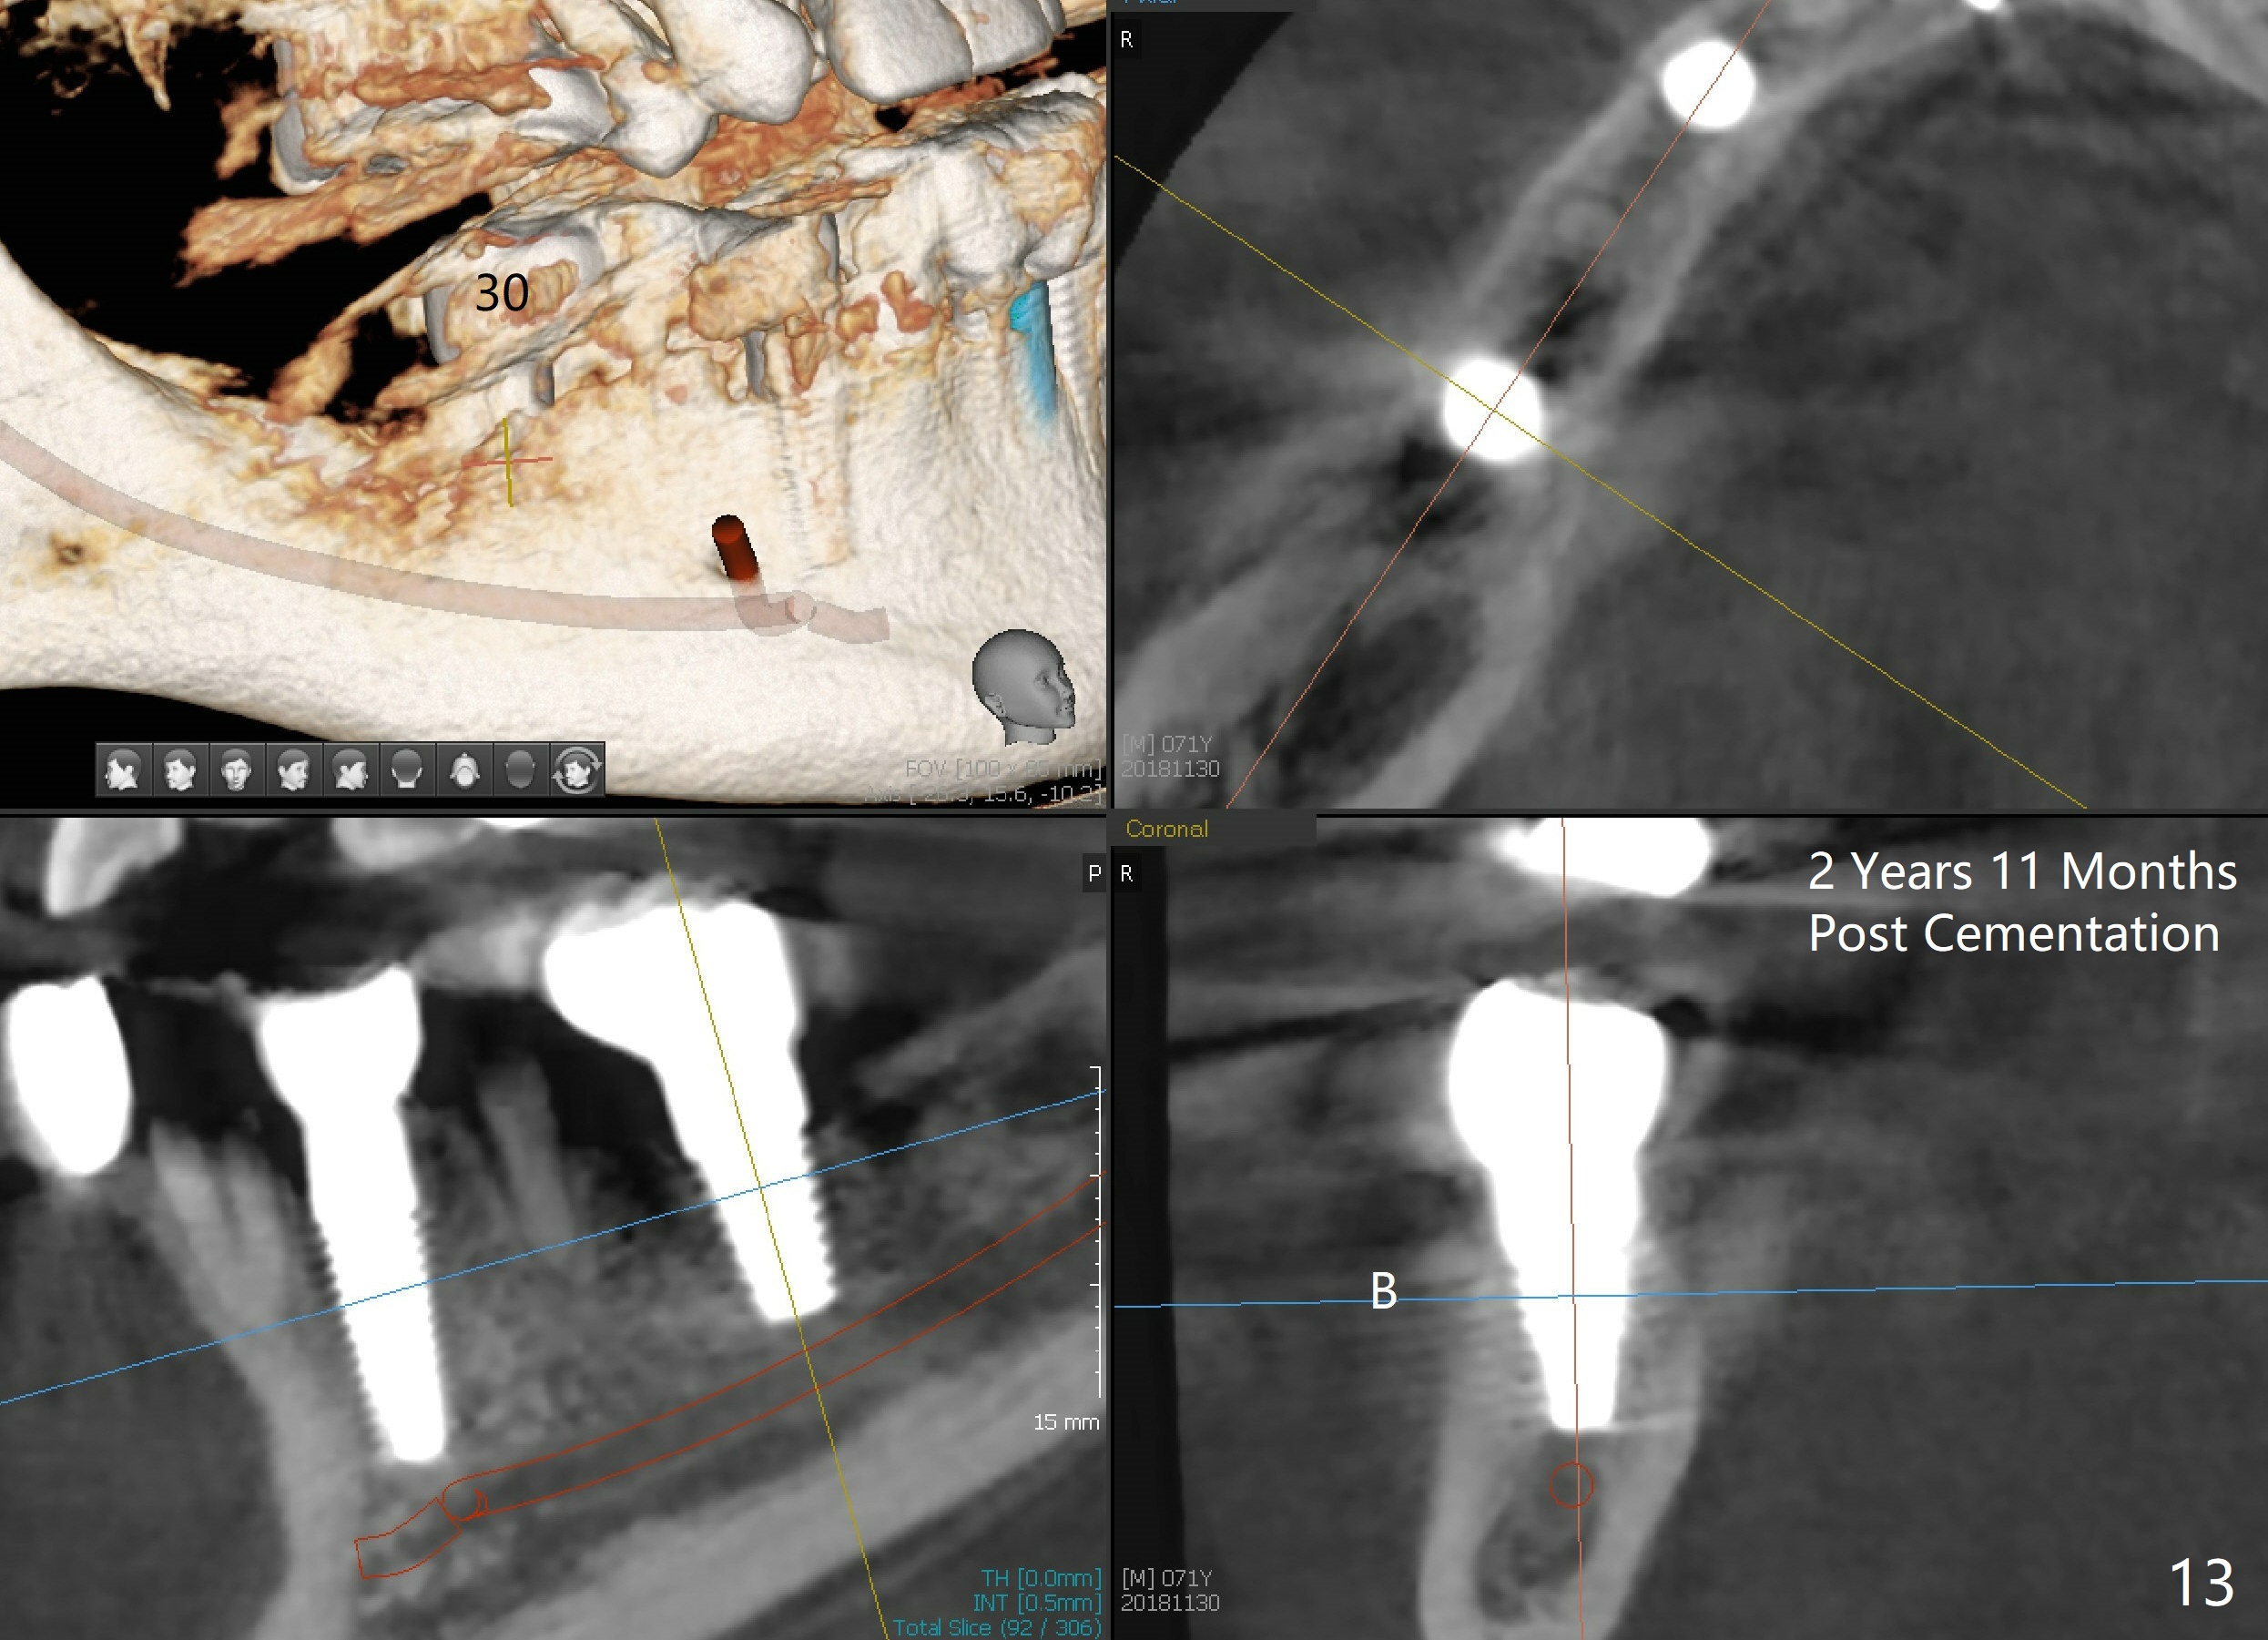

Placement of implant at the site of #30 is a part of full mouth reconstruction aided by orthodontic treatment (1). As Fig.3 demonstrates, the tooth #29 is supraerupted (arrow). Once the implant at the site of #30 is osteointegrated, it is used as one of anchorages (the other is #28 implant crown) to intrude #29. In fact, the patient is uncooperative in orthodontic treatment. There is cortical bone-like formation 3 years postop, 1 year 10 months post cementation (Fig.12 <). There is no bone loss 2 year 11 months post cementation (Fig.13 CT).